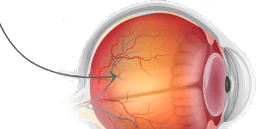

Lutexid tiene un efecto beneficioso sobre los músculos oculares: previene la hipertonicidad, alivia la fatiga, ayuda al cristalino a enfocar correctamente y garantiza una imagen nítida y clara.

Los componentes naturales de Lutexid actúan específicamente sobre el origen de la inflamación, alivian la irritación, las molestias y el dolor.

Lutexid ayuda a aumentar el número de células sensibles a la luz, lo que mejora la claridad, la nitidez y la agudeza de la visión, y garantiza una correcta reproducción de los colores y una excelente visión crepuscular y lateral.